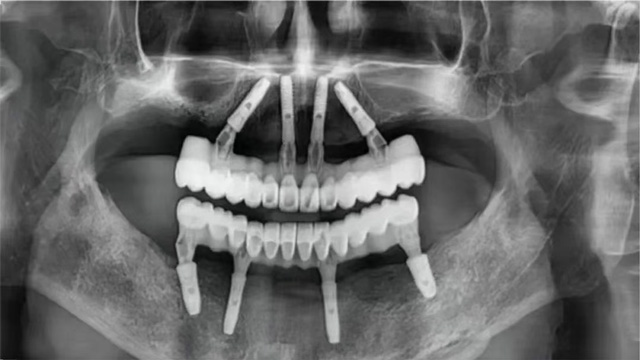

全口种植手术完成后,张先生感觉不错。稍事休息后完成了即刻修复,戴上了临时牙冠。几个月后,张先生回院复诊,戴上了正式牙冠。看着镜子里一排整齐又漂亮的牙齿,他露出了久违的笑容。

全口无牙颌即拔即种术后全景片

10年后,他庆幸自己选择了新桥口腔这样的医疗机构,庆幸遇到姜辰主任样有技术、有经验的医生,通过种植8颗种植体恢复了全口咀嚼功能,让他在晚年得以重拾口福。

张先生重获24颗牙